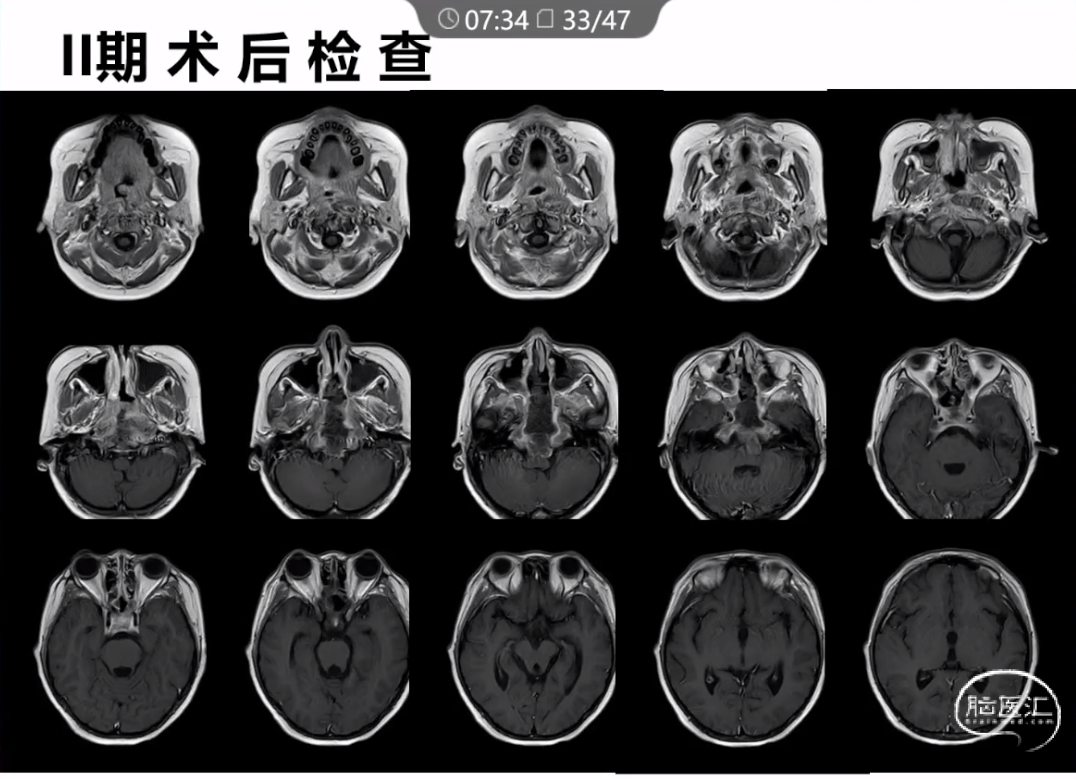

本文主要内容为:脊索瘤临床特点、治疗选择,以及多个手术病例。